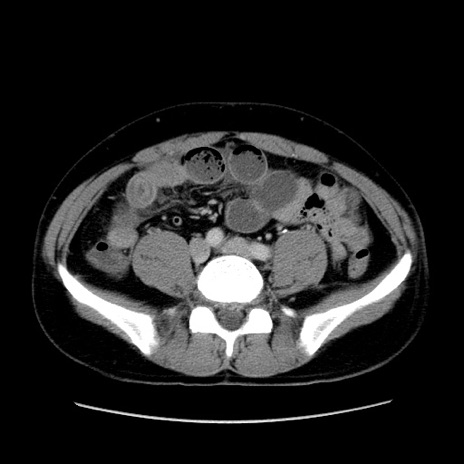

冠状断像

【症例】30歳代男性

【主訴】腹痛、嘔吐

【現病歴】昨晩から突然の腹痛あり、その後嘔吐、軟便も出現。腹痛が改善しないため救急搬送となる。2日前にしめ鯖の食事歴あり。

【身体所見】意識清明、苦悶様、BP 135/90mmHg、BT 35.7℃、腹部:平坦、やや硬、心窩部〜臍部に自発痛、圧痛あり、筋性防御+、反跳痛-

【データ】WBC 8100、CRP 0.57